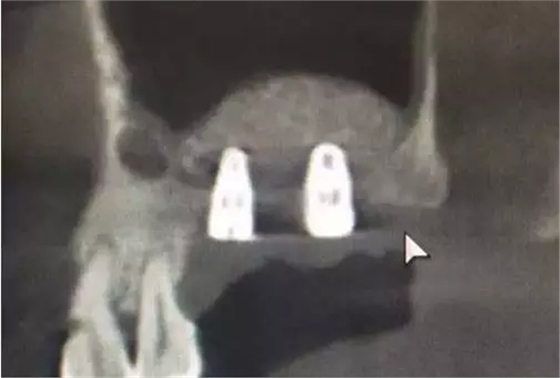

術(shù)后6,7牙位CT片,顯示充足的植骨量。